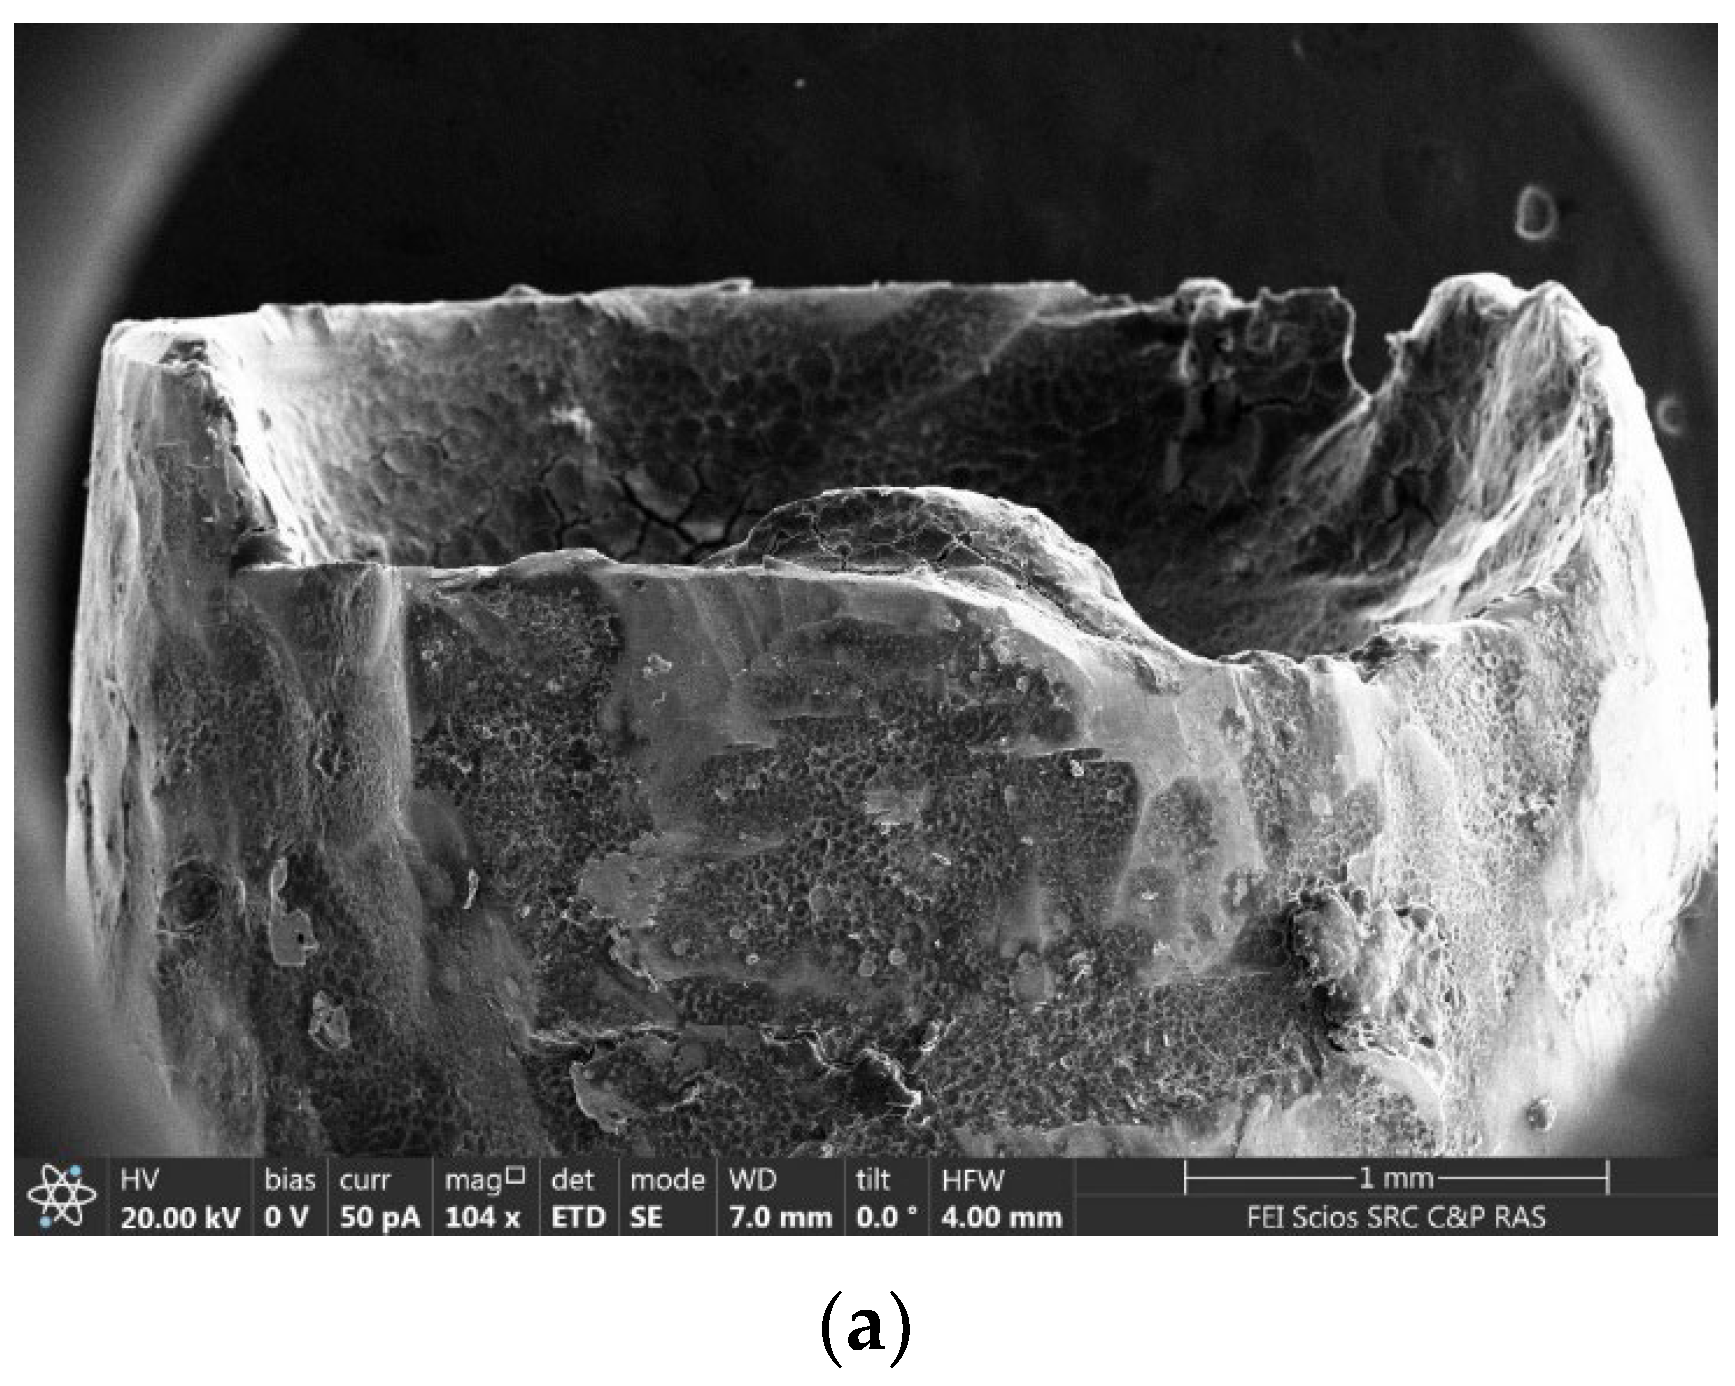

2.1.1. Results of X-ray and Electron Microscopic Studies

4.4. Methods of Scanning Electron Microscopy (SEM) and Transmission Electron Microscopy (TEM) with Energy Dispersive (ED) Analysis